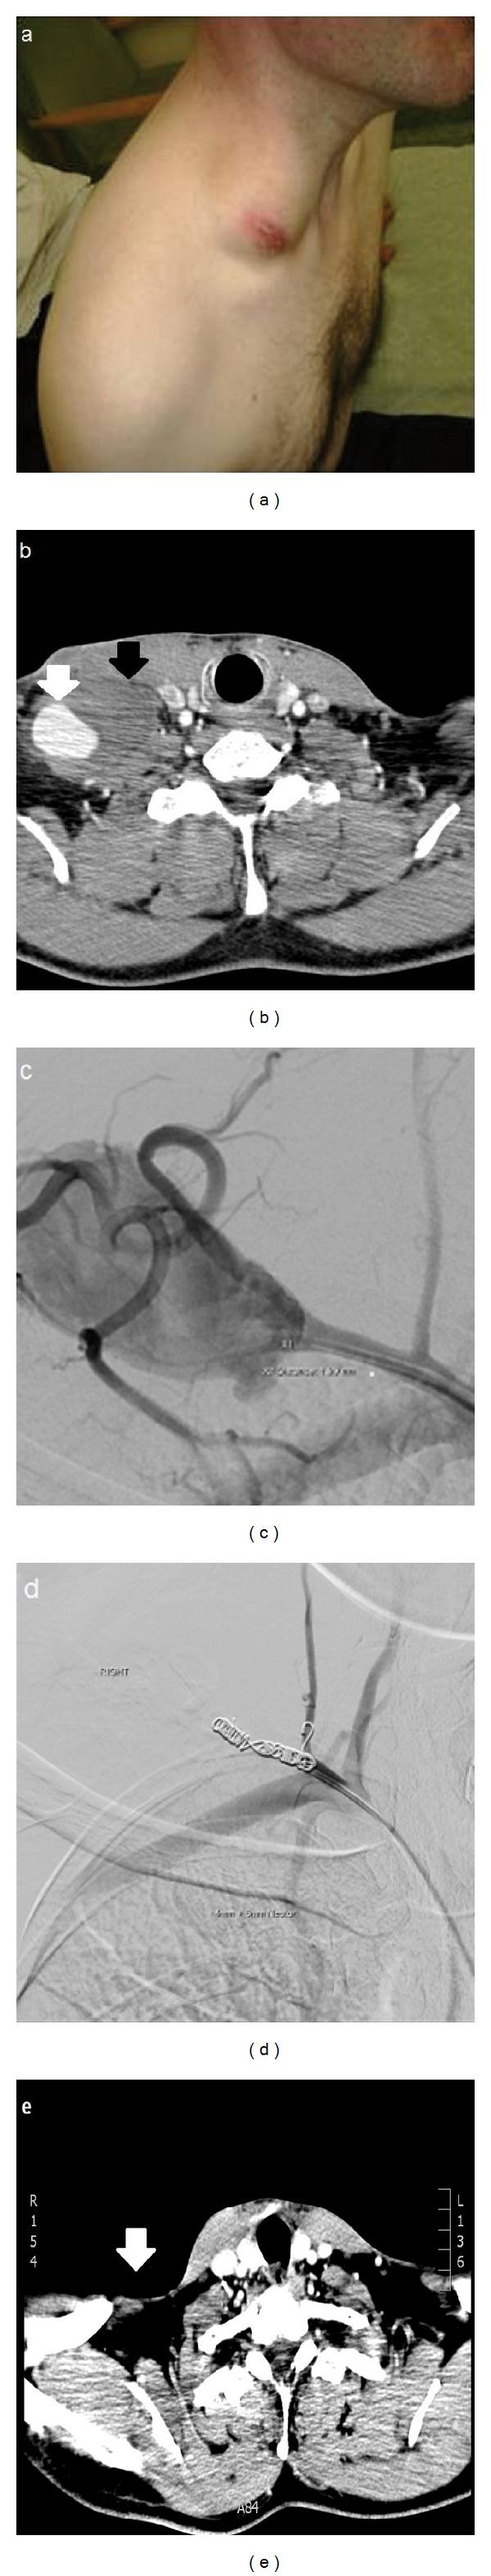

A pseudoaneurysm is a haematoma which is surrounded by connective tissue and communicates with the lumen of a ruptured blood vessel. It has no true defined capsule. We describe a case of tuberculous pseudoaneurysm. This is a rare complication of tuberculosis. The clinical presentation of these lesions is highly variable. Definitive diagnosis should consist of contrast-enhanced CT and arteriography. Treatment should include repair of the arterial wall by surgery, endovascular stent-graft insertion, or embolization followed by a full course of antituberculous chemotherapy. Our case is highly unusual in that the pseudoaneurysm arose from the subclavian vasculature in a patient with extrapulmonary tuberculosis only.

假性动脉瘤是一种被结缔组织包围并与破裂血管腔相通的血肿。它没有真正明确的包膜。我们描述了一例结核性假性动脉瘤病例。这是结核病的一种罕见并发症。这些病变的临床表现高度多变。确诊应包括增强CT和动脉造影。治疗应包括通过手术修复动脉壁、血管内植入支架移植物或栓塞,随后进行全程抗结核化疗。我们的病例非常特殊,因为假性动脉瘤仅在一名肺外结核患者的锁骨下血管系统中出现。